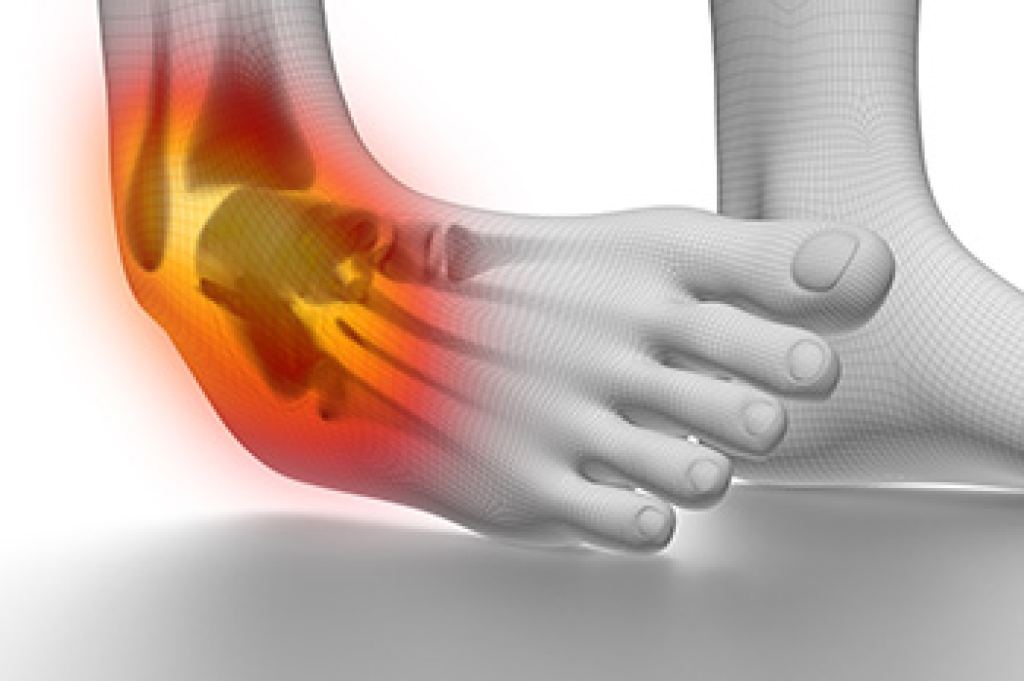

Broken ankles are common injuries that can involve various fractures of the bones in the ankle joint, primarily the tibia, fibula, and talus. A fracture can occur from a sudden twist, fall, or impact, leading to symptoms such as intense pain, swelling, bruising, and difficulty bearing weight. There are several types of ankle fractures, including stable fractures, where the bones remain aligned, and unstable fractures, where the bones shift out of place. Stress fractures can also develop over time due to repetitive impact. Treatment depends on the type and severity of the fracture. Minor fractures may require rest, while more serious fractures often necessitate immobilization with a cast or splint. In some cases, surgery may be needed to realign the bones. If you suspect an ankle fracture, it is suggested that you schedule an appointment with a podiatrist for a thorough evaluation and tailored treatment plan.

A broken ankle is experienced when a person fractures their tibia or fibula in the lower leg and ankle area. Both of these bones are attached at the bottom of the leg and combine to form what we know to be our ankle.

When a physician is referring to a break of the ankle, he or she is usually referring to a break in the area where the tibia and fibula are joined to create our ankle joint. Ankles are more prone to fractures because the ankle is an area that suffers a lot of pressure and stress. There are some obvious signs when a person experiences a fractured ankle, and the following symptoms may be present.